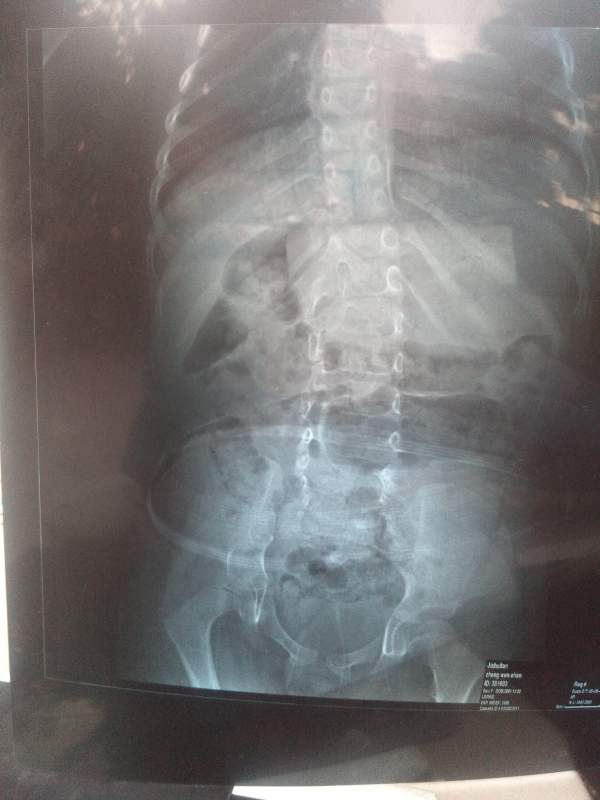

ÃÃÃÃÒòÖÎÁÆÑÓÎó£¬ÏÖ²¡Çé¼ÓÖØ£¬ÃæÁÙ̱»¾£»Õ÷Çó¸÷λ³æÓÑÌá³ö±¦¹óµÄÒâ¼û£¬½«¸Ð¼¤²»¾¡